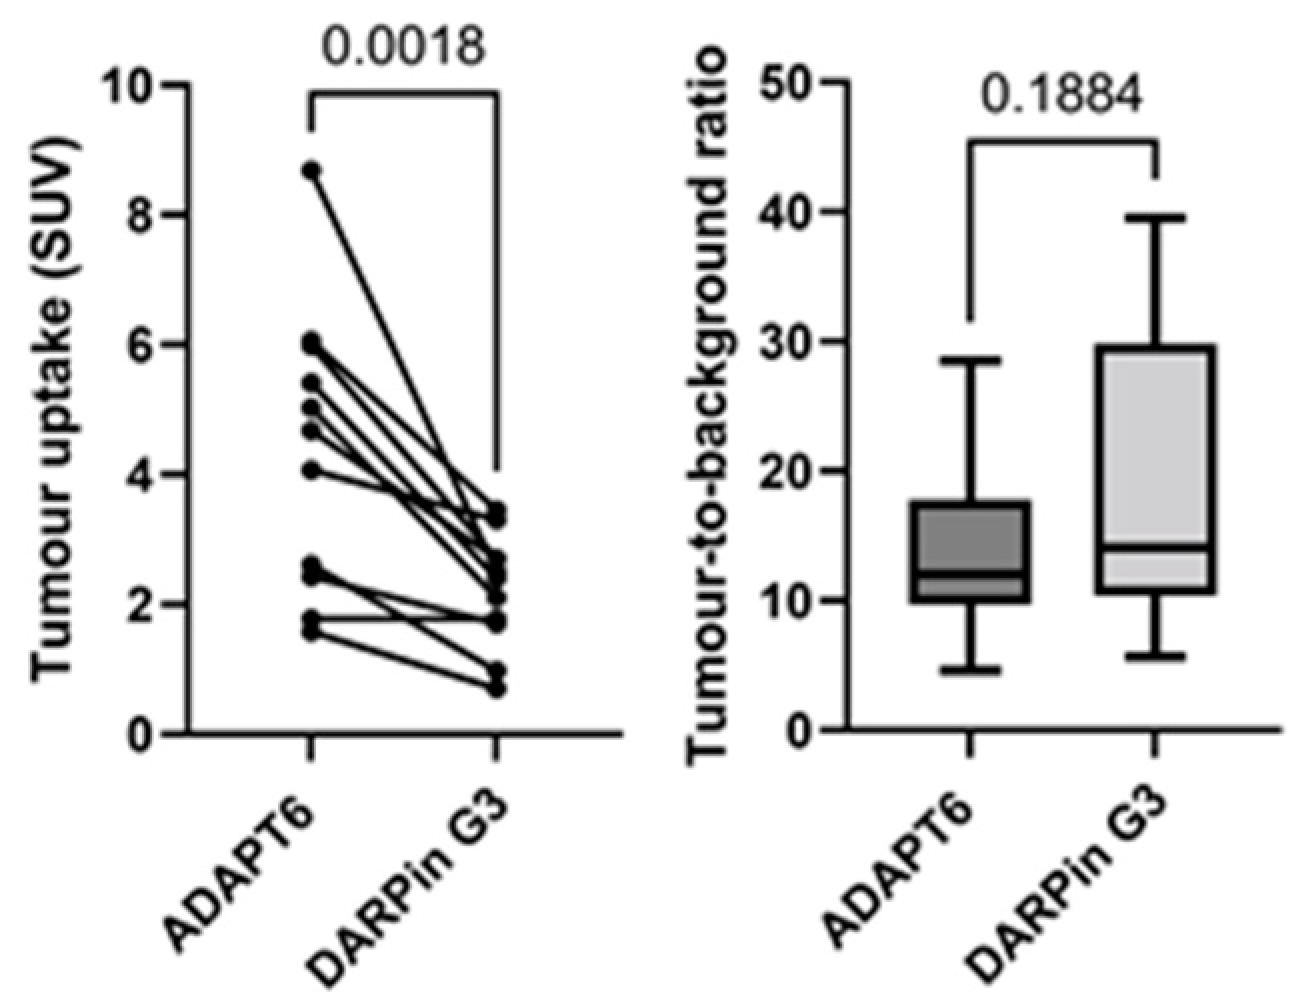

3. Results

4. Discussion